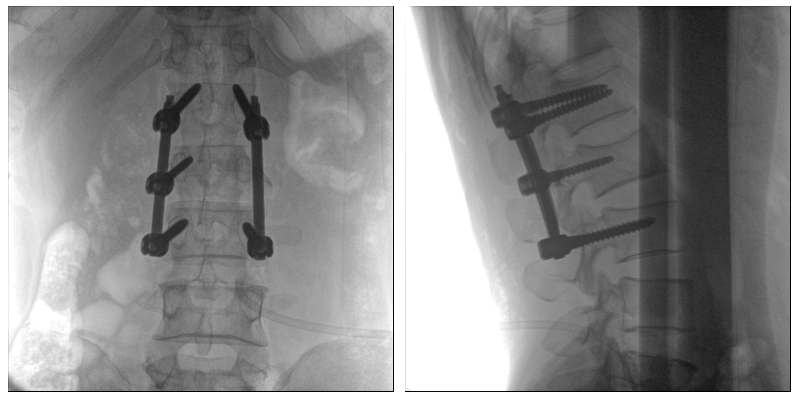

從下圖中可以看到二維影像能夠提供目標(biāo)區(qū)域在某一個平面的重疊影像,雖然因為人體不同組織的密度差異,使得圖像具有較為豐富的信息量,但組織間的相互重疊還是會出現(xiàn),諸如空間位置等眾多信息在影像中遺失或不可辨認(rèn)的情況,影響了醫(yī)生對信息的收集與應(yīng)用。

術(shù)中二維影像

而三維影像的MPR圖像組可以通過不同平面的切分,使成像區(qū)內(nèi)更豐富的信息得以呈現(xiàn)。尤其是二維影像無法涉及的橫斷面,提供了另一個空間維度的信息量。

術(shù)中三維C臂影像